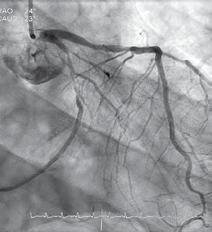

Fig. 5: Coronary Three-Vessel Disease: LAD, Cx, RCA

Fig. 7: right common iliac stenosis, occlusion of superficial femoral artery bilateral

Fig. 8: LIMA on LAD and two vein grafts on Cx and RCA

Fig. 6: Carotid TEA